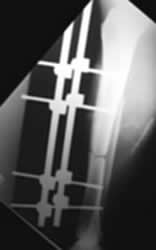

Fig 92. Clavo de Enders.

A: Rx AP. Fractura espiroidea y con angulación en valgo, de la diáfisis humeral.

B: Rx AP. Reducción abierta y fijación intramedular, con clavo de enders.